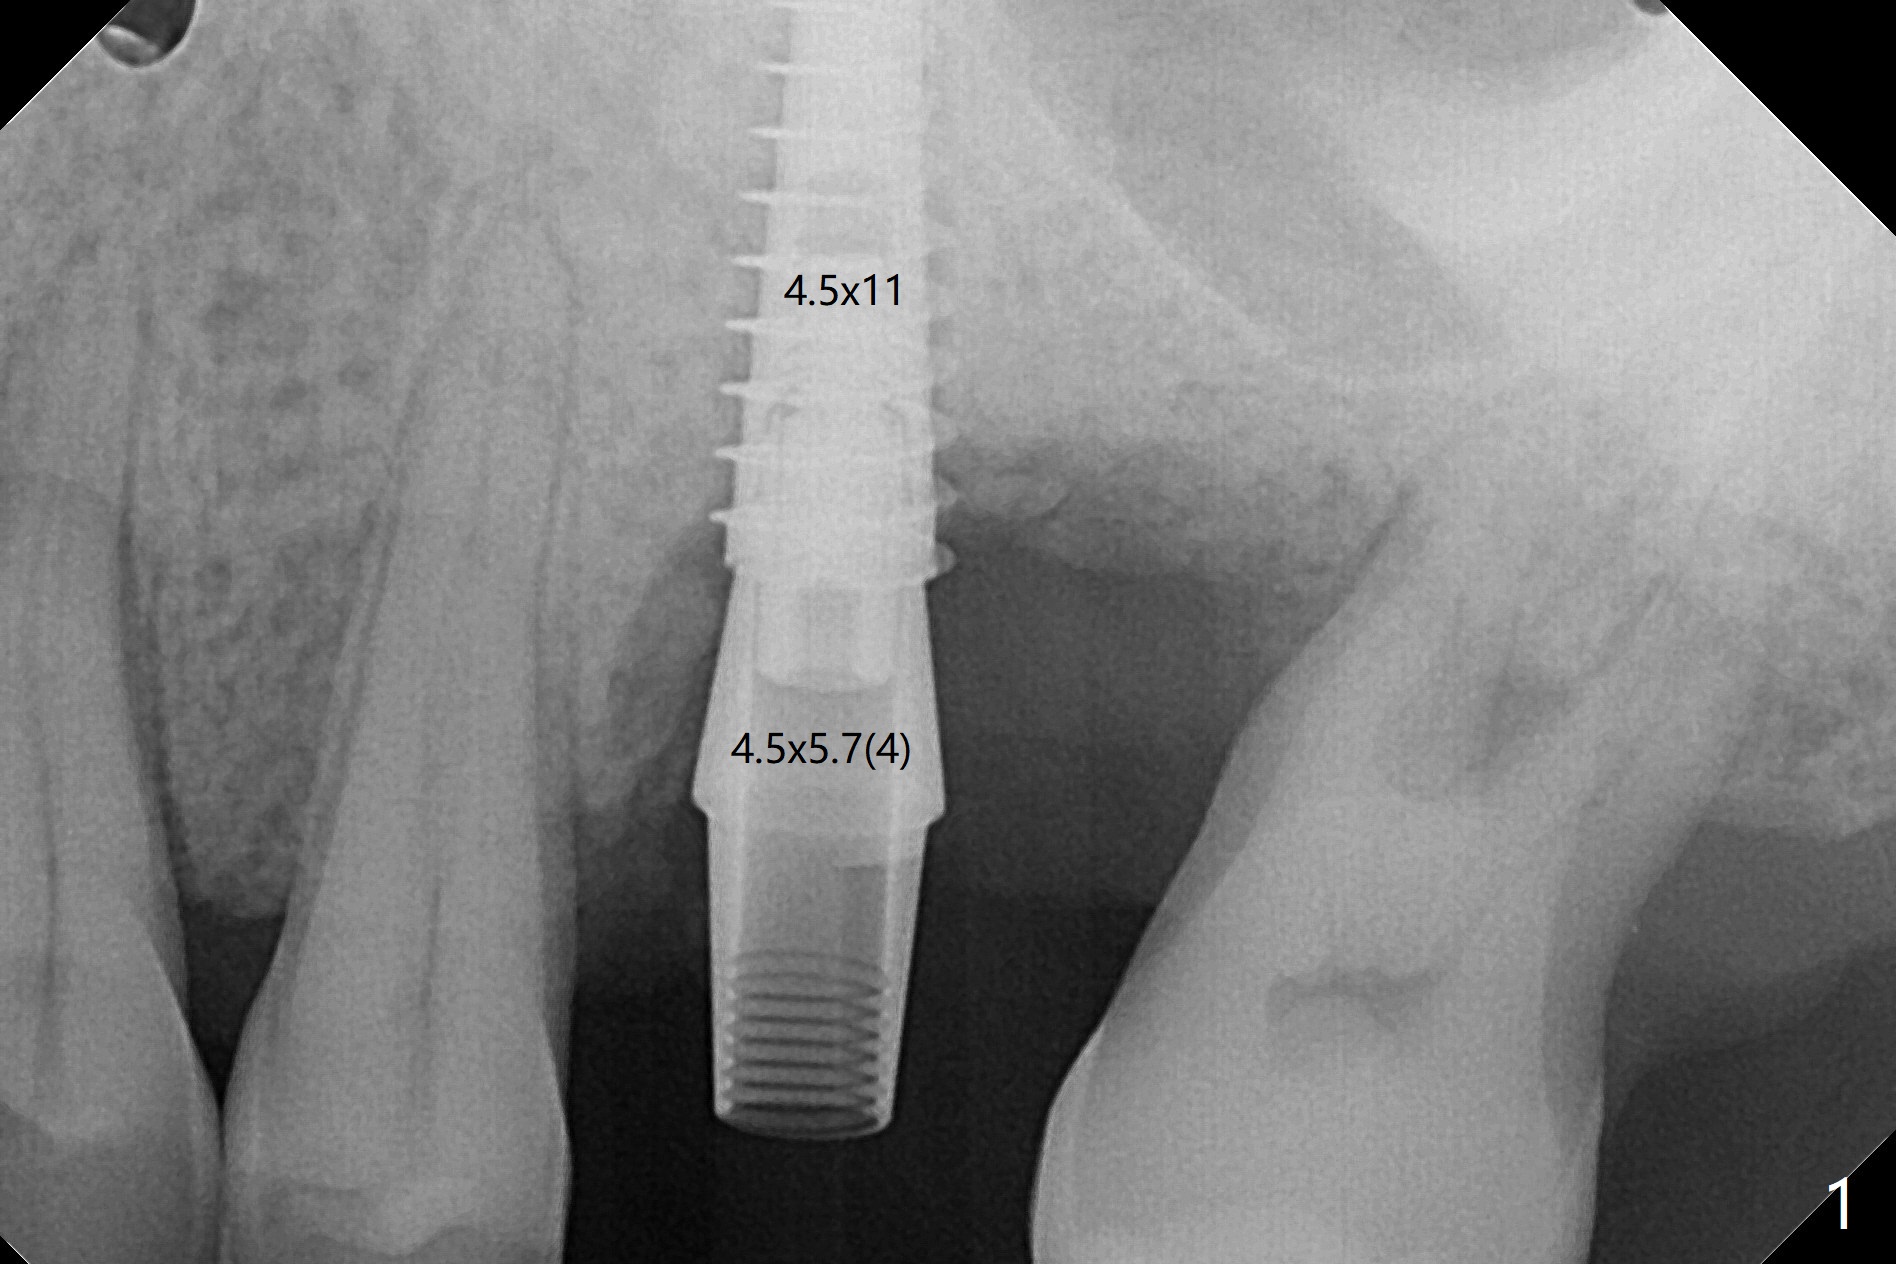

50岁男左上6严重斜型骨质吸收(意味着牙龈特别厚,有可能植入许多骨粉),拔除近中残根后,切开翻瓣,利用导板,4.5x11毫米植体不仅有意近中植入(补偿斜型骨质吸收而造成远中偏移),而且种得表浅(避免使用异常长的基台,改善冠根比例,图一),之后堆入不少粘性骨粉(图二:*),覆盖PRF膜,减张缝合(挺困难),牙周敷料。术后两周,敷料脱落,伤口裂开,但愿骨粉丢失不会太多(图三,四),树脂敷料可能更稳当。术后4个月骨粉好像覆盖远中曾经暴露螺纹(图五:^)。术后四个月伤口愈合(图六),临时牙冠大约3个月。粘固前局部牙龈健康,螺丝扭力30 Ncm。